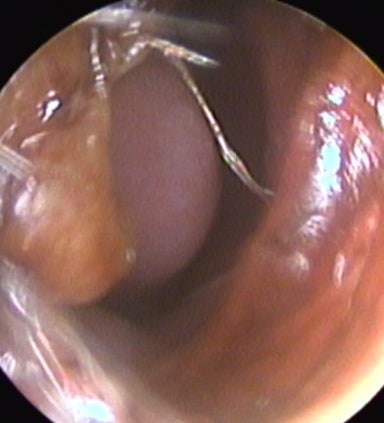

Busan Seongseo Hospital’s otorhinolaryngology department tells you about nosebleed. Nosebleed is a word that we know well.Regardless of age or gender, it can occur due to various causes such as blood, heart, kidney, liver, trauma, etc. Especially in children under adolescence, there is a lot of repeated bleeding in small amounts, and in older age, there is frequent bleeding with hypertension and arteriosclerosis.

How should non-bleeding be treated?In the event of an unexplained non-hemorrhage, it is important to stop bleeding first.I recommend you to close your nose and lower your head to stop bleeding.I spit out the blood that came into my mouth without swallowing it.Also, if you feel the spot where the bleeding occurred in front of your nose, it is effective to press it with a clean cotton or hand for about 5-10 minutes and lightly compress it with cold ice or water.However, if you can’t stop bleeding by the method I mentioned earlier, or if it is judged to be severe, the best way is to visit an otolaryngologist for a diagnosis.If non-bleeding occurs repeatedly, you may have to undergo nasal septum surgery because of suspected nasal septum curvature, and if the bleeding is severe, you may have to be hospitalized for blood transfusion, so don’t take it too lightly.